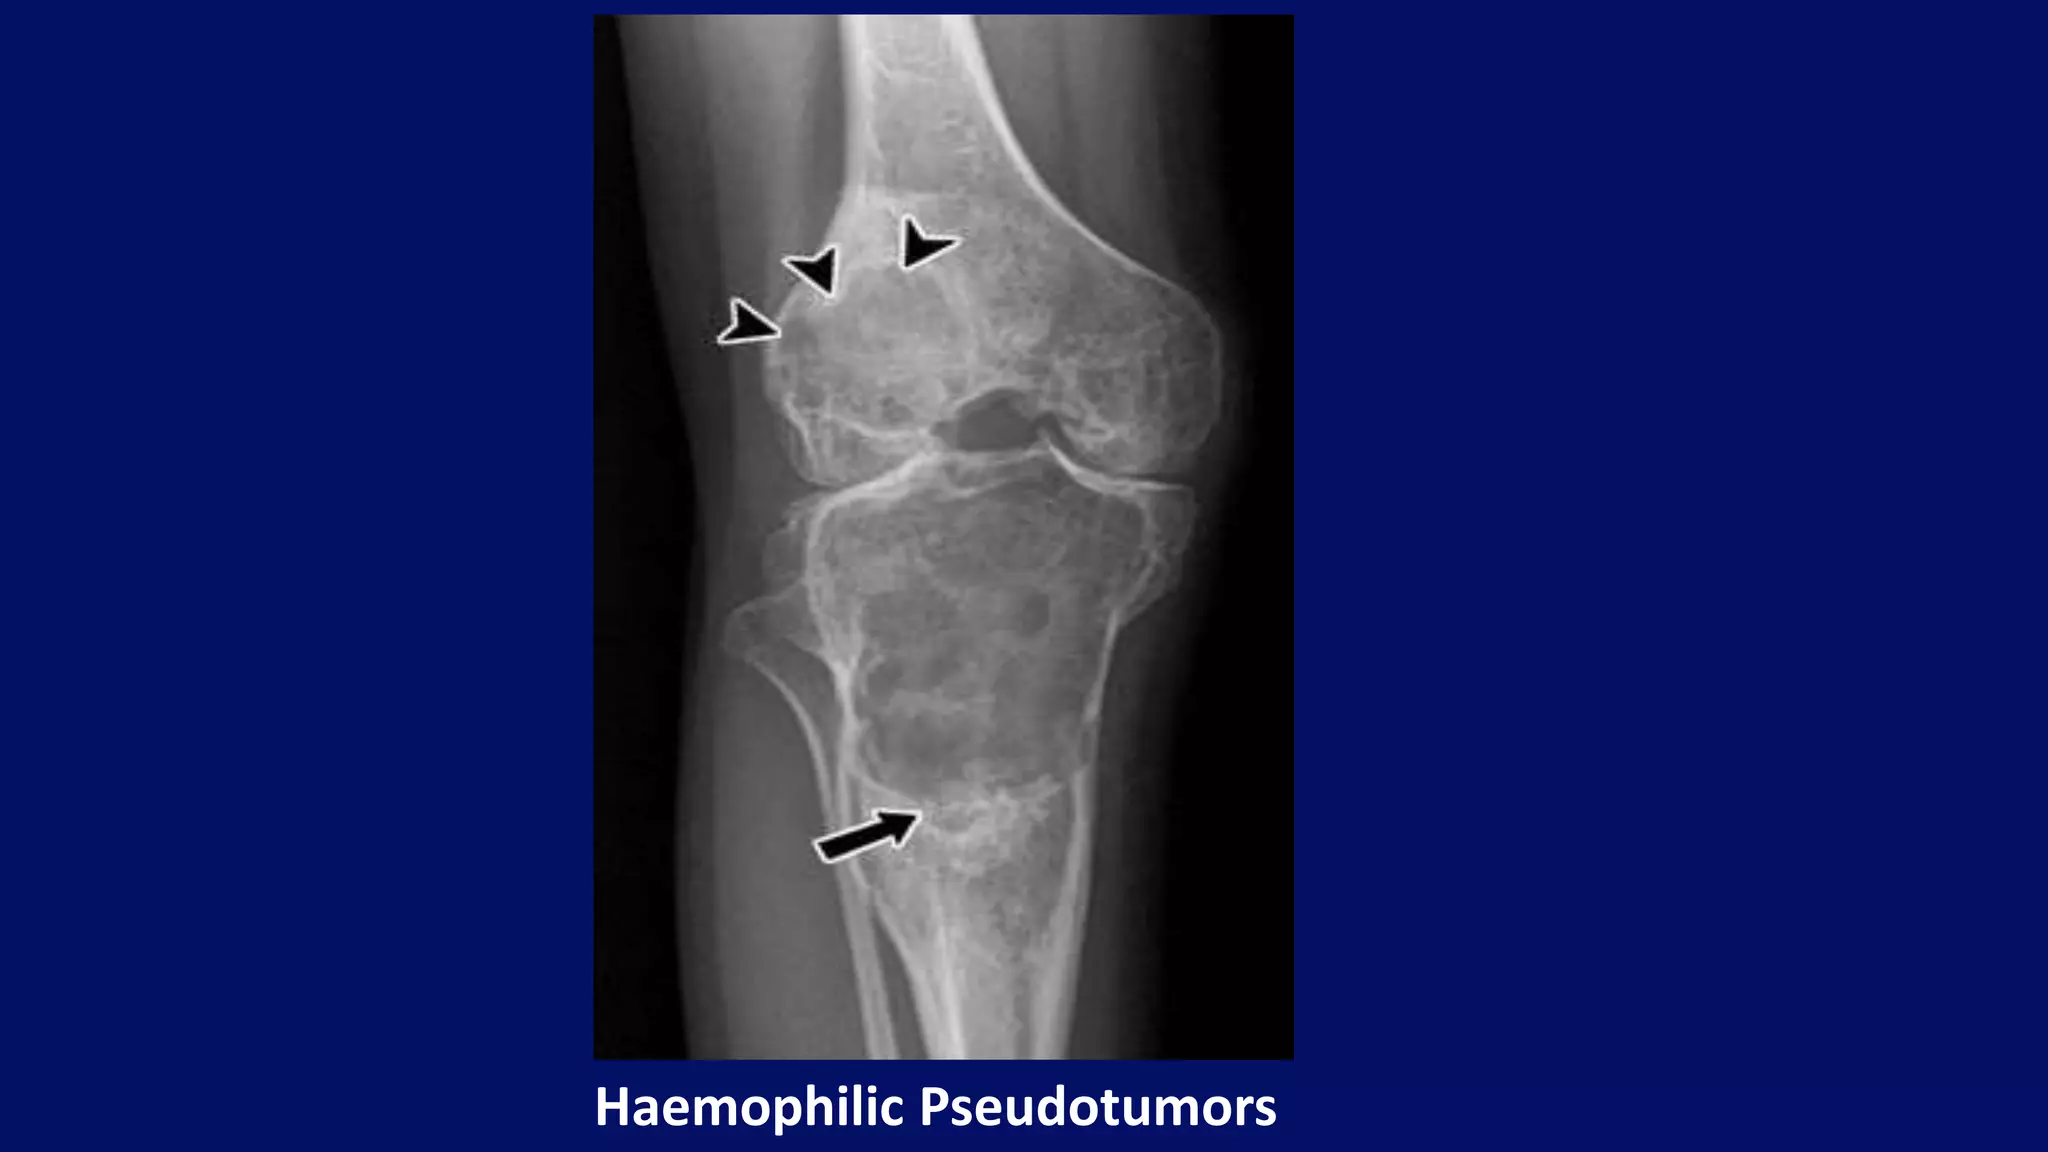

Haemophilic Pseudotumors

• haemophilic pseudotumours

• #121 27-year-old man with hemophilia and two osseous pseudotumors in right lower extremity, new lesion at distal femur (arrowheads). In tibial lesion, septa have thinned or disappeared, although new irregular calcifications (arrow) have developed within distal region. Most develop in the muscles of the pelvis and lower extremity, where the large muscles have a rich blood supply, or in bone following intraosseous bleeding. Pseudotumours appear as well defined,unilobular or multiloculated, lytic, expensile lesions of variable size. It can involve metadiaphysis and epiphysis of long bones.